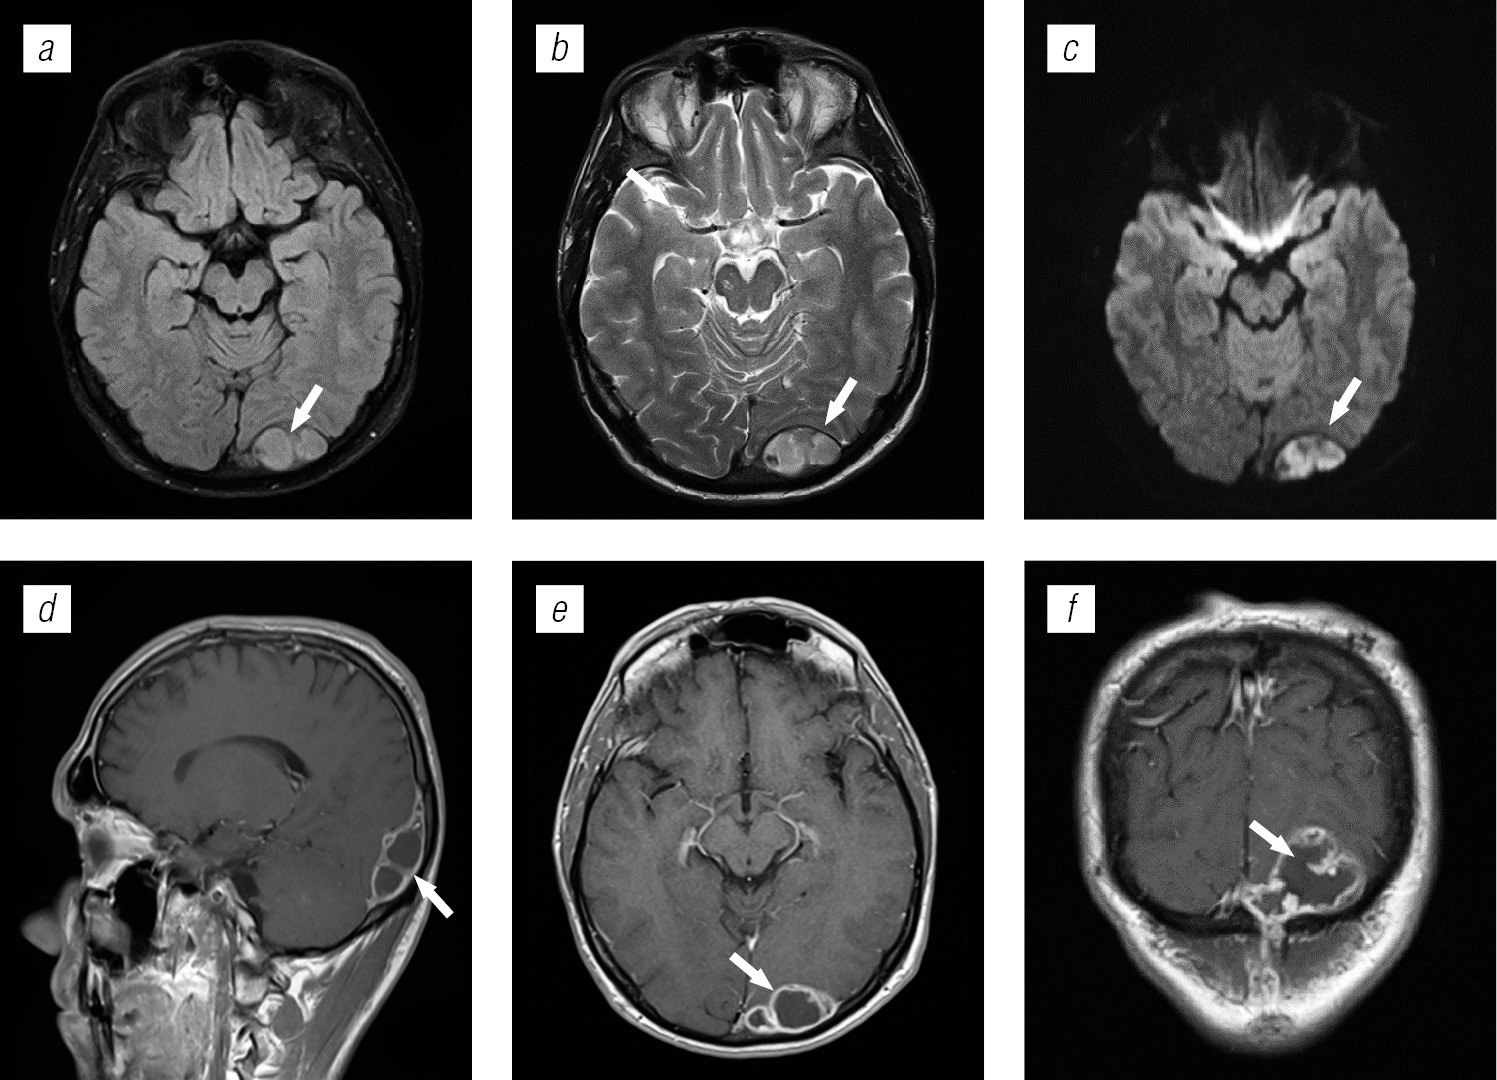

Структура оппортунистических и вторичных заболеваний была представлена токсоплазмозом головного мозга (18,3 %), герпесвирусными поражениями (12,2 %), прогрессирующей мультифокальной лейкоэнцефалопатией (10,24 %), нейроинфекцией неуточненной этиологии (12,2 %), криптококкозом (4,39 %), туберкулезом (2,44 %), лимфомой головного мозга (2,44 %), МАК-инфекцией (0,24 %).

Поражение головного мозга у ВИЧ-инфицированных больных во многом характеризуется синхронностью (микст-инфекция в 8,52 %) и мультифакторностью поражения.